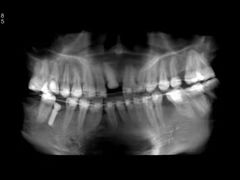

• -联合口腔(西环诊所)

在丽江古城跳舞的炒鸡蛋 | 21-05-08

报错